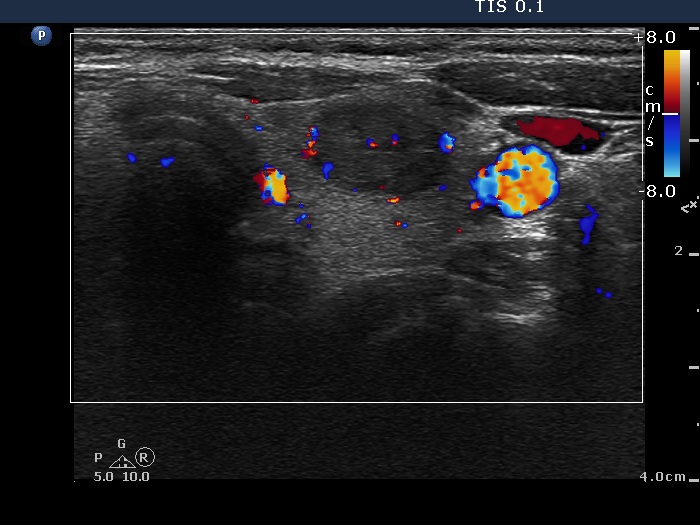

Intranodular hyperechogenic figures - case 1789 (ultrasonographic picture 7)

Left lobe, transverse view, color Doppler mode. Although the lesion presents signs of perilesional blood flow, this pattern is not specific.